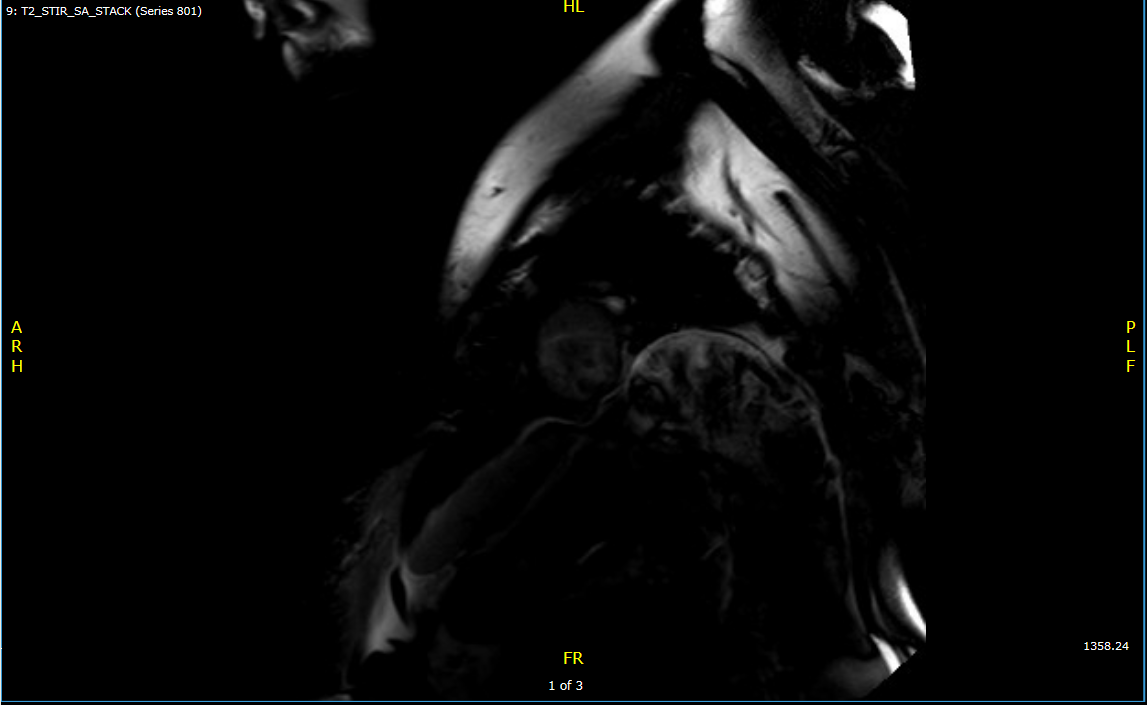

Cardiac MRI: Diffuse circumferential pericardial thickening. No increased pericardial enhancement. No pericardial delayed enhancement. Features of constriction are present with a mild septal bounce, mild conical deformity, diastolic restraint, and dilation of the suprahepatic IVC.

Figure 1: T2 STIR MRI showing no pericardial edema